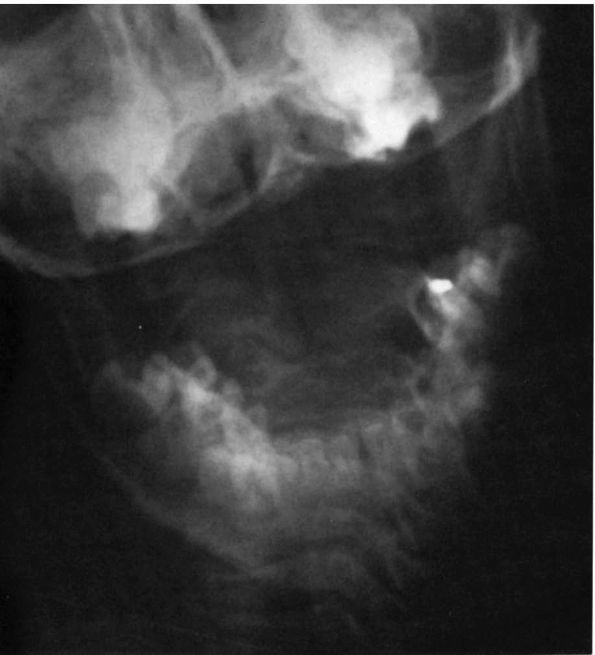

FIGURE 11-1.

Torticollis is head tilt with rotation. Congenital muscular torticollis and rotatory subluxation of the atlas on the axis are the two most common causes in children. Facial asymmetry is present. |